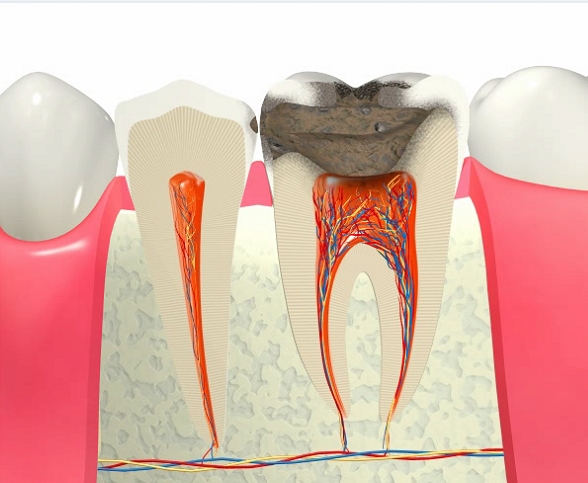

虫歯の進行

早期発見・早期治療を

虫歯は急激に進行する訳ではなく、時間をかけて進行していきます。

ごく初期段階であるC0(経過観察)を過ぎると、虫歯はどんどん悪くなっていきます。歯は一度悪くなれば元の状態に戻ることはないということをしっかり理解しておくことが大切です。

歯科医院では虫歯は進行段階によって「C0」「C1」「C2」「C3」「C4」という記号で表し、初期段階のC0の段階であれば適切な処置を行えば歯を削ることなく再石灰化によって自然治癒することも可能です。 しかしながら、それ以降のC1~C4という段階の場合は歯科医院で治療を行う必要があります。

C1 エナメル質が溶けて表面に穴があいた状態

虫歯の初期段階がC1です。この段階では虫歯を削ってレジン(プラスチック)を詰め、1回で治療を完了させることが出来ます。

C2 虫歯が象牙質にまで広がった状態

C2の段階になると、冷たいものが染みるようになります。この段階までなら歯を削る量を出来るだけ少なくすることが可能です。治療回数も1~2回程と、比較的短期間で治療が完了します。

C3 歯がかなり失われてしまった状態

C3まで進行すると、痛みなどの自覚症状はC2の時よりも多くなります。この段階以降は虫歯が神経まで達してしまっているため、一般的には神経を取り除く治療を行うことになります。

C4 歯の根だけしか残っていない状態

この段階まで虫歯が進行しまうと、残念ながら基本的には歯を残すことが出来なくなってしまいます。ただし、歯の根や周囲の骨の状況などによっては歯を残すための治療が可能な場合もありますので、まずは当院までご相談ください。

※虫歯がC4の段階まで進行すると、通常の場合、痛みはなくなります。 痛みがなくなると「歯科医院に行って治療しなくてもいいか」と考える方も少なくありませんが、これは非常に危険です。なぜなら、痛みが消えたのは虫歯が治ったからではなく、歯の神経(歯髄)が死んでしまったからです。その間にも歯は細菌によって溶かされ、腐らされています。早めに歯科医院を受診するようにしましょう。

虫歯の痛みの原因

虫歯の痛みはなぜ起こる?

それは、歯の中にある神経がとても原始的であり、未発達なものだからです。

人間が感じることが出来る感覚には「痛覚」の他にも「温度感覚」や「圧覚」などが存在しますが、歯の神経は未発達なため、あらゆる刺激を「痛み」として認識してしまうのです。

また、周囲を歯という硬い組織で囲まれているため、一度そのような刺激を感じて歯の中の血管や神経に炎症が起きると、自己破壊的にどんどん進行していってしまいます。虫刺されと同じように、炎症というのは組織のボリュームが増加し膨れ上がることです。これが歯の中で起こると、組織ごと除去する治療を行わなくてはいけなくなってしまいます。これが抜髄と呼ばれる、歯髄組織を除去するための治療です。